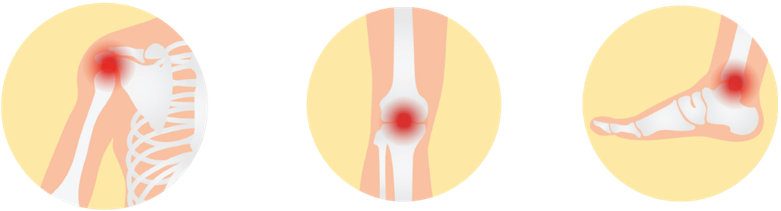

骨关节炎,顾名思义,就是因为关节老化、磨损引起,常见于50岁以上的人群。最容易引发骨关节炎的关节是膝关节,接着便是髋关节。

多数由上呼吸道感染的病菌(溶血性链球菌)引发的关节炎,发病人群大部分是小孩和青少年。感染了风湿性关节炎容易受影响的部位是肩、肘、膝、踝关节等大关节。

我们最常受风寒湿邪影响的就是我们的肩颈、膝盖和脚踝。肩颈和膝盖多数会因为外露而缺乏保暖,在吹到风或下雨淋湿后就容易受寒;而脚踝则是因为在日常活动中使用的次数太多,感受了风寒湿邪后,气血循环受影响,局部的循环受阻引起疼痛。